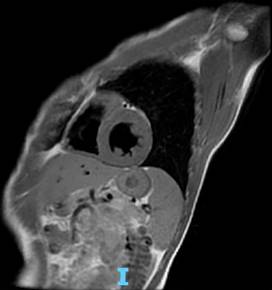

Caso clínico 2: hombre de 30 años, originario de Ciudad de México. Sin antecedentes hereditarios de importancia. Con hipertensión arterial sistémica de 10 años de diagnóstico, tratado con nifedipina 30 mg cada 24 horas; en adecuado control. Diagnóstico de insuficiencia cardiaca congestiva en tratamiento con sacubitrilo/valsartán 50 mg cada 24 horas y carvedilol 12.5 mg cada 24 horas. Hallazgos en resonancia magnética cardiovascular: ventrículo izquierdo ligeramente dilatado con septum de 11 mm, pared posterior del ventrículo izquierdo de 7 mm, diámetro diastólico del ventrículo izquierdo de 55 mm, Diámetro sistólico del ventrículo izquierdo de 45 mm con índice de volumen tele diastólico de 108 mL/m2 e índice de volumen telesistólico de 56.4 mL/m2, masa miocárdica de 143 g con fracción de acortamiento de 18% y fracción de eyección de 48%. Evidencia de hipocinesia septal e inferior a nivel basal y en la pared septal apical. Diagnóstico de cardiopatía dilatada (Figura 2).

Figura 2: Cardiorresonancia magnética del caso clínico 2. Corte sagital con secuencia de inversión recuperación (IR) doble, con evidencia de cardiomiopatía dilatada.